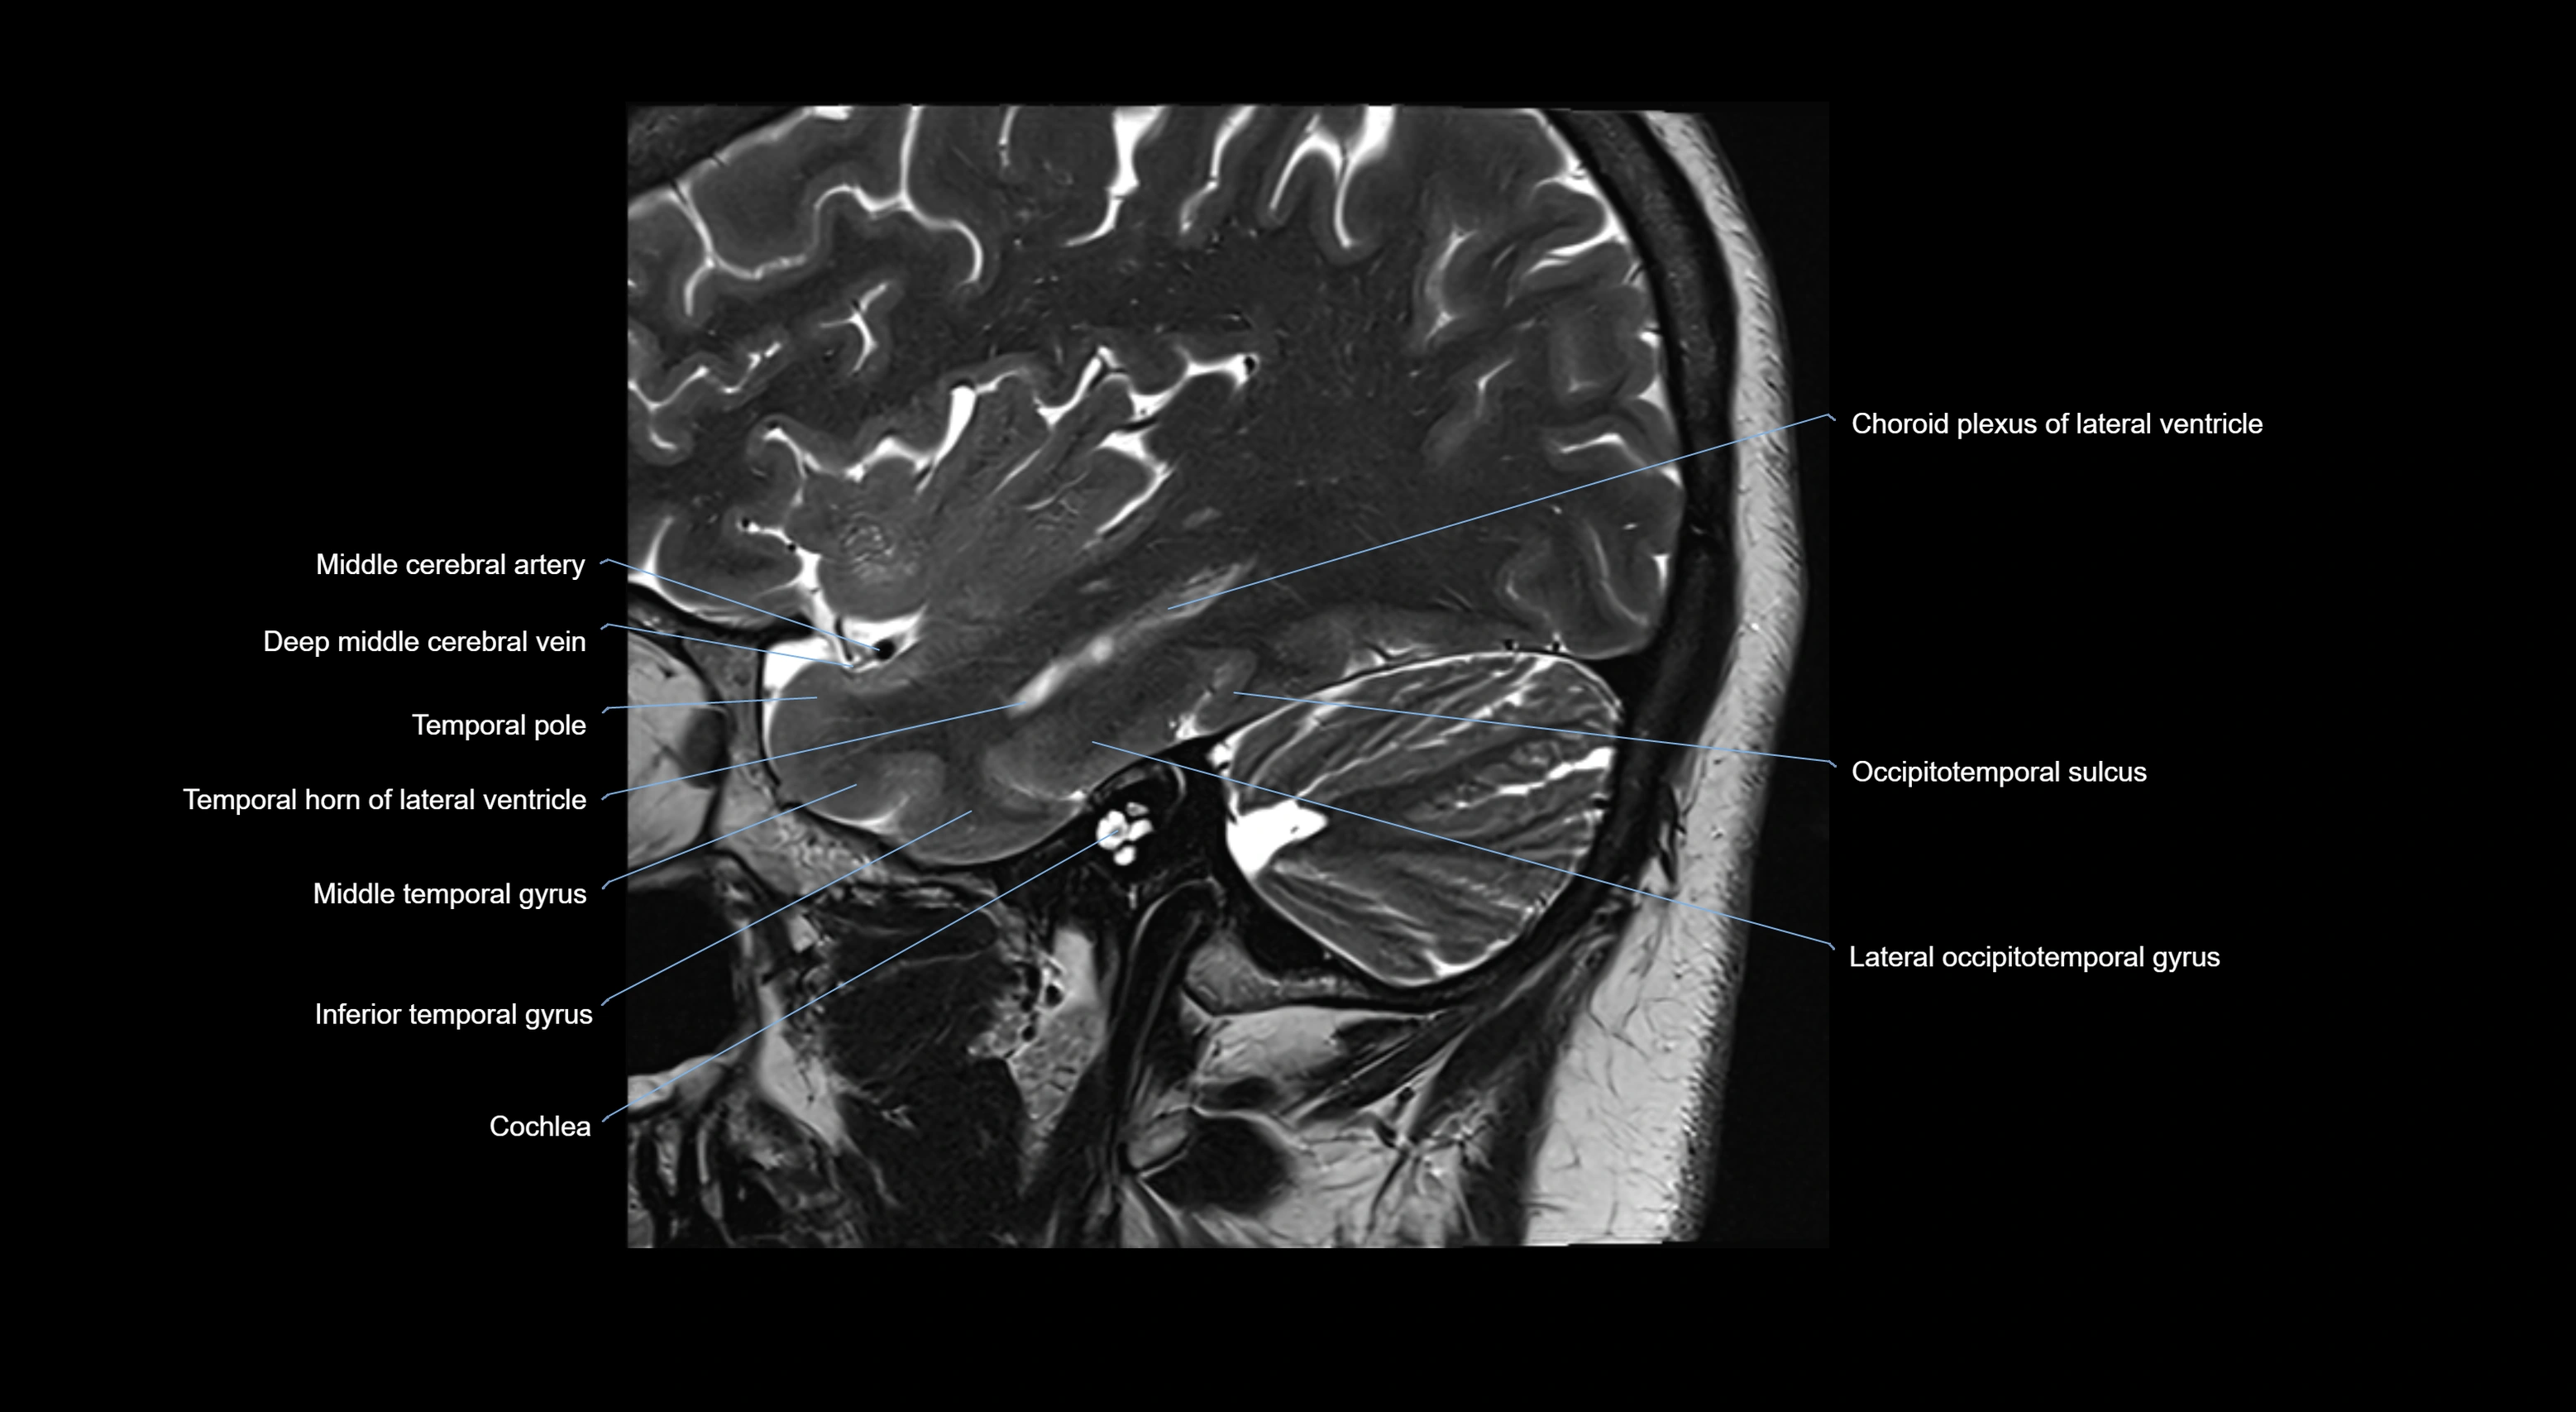

- Choroid plexus of the lateral ventricle

- Cochlea

- Deep mddle cerebral veins

- Middle cerebral artery

- Temporal horn of lateral ventricle